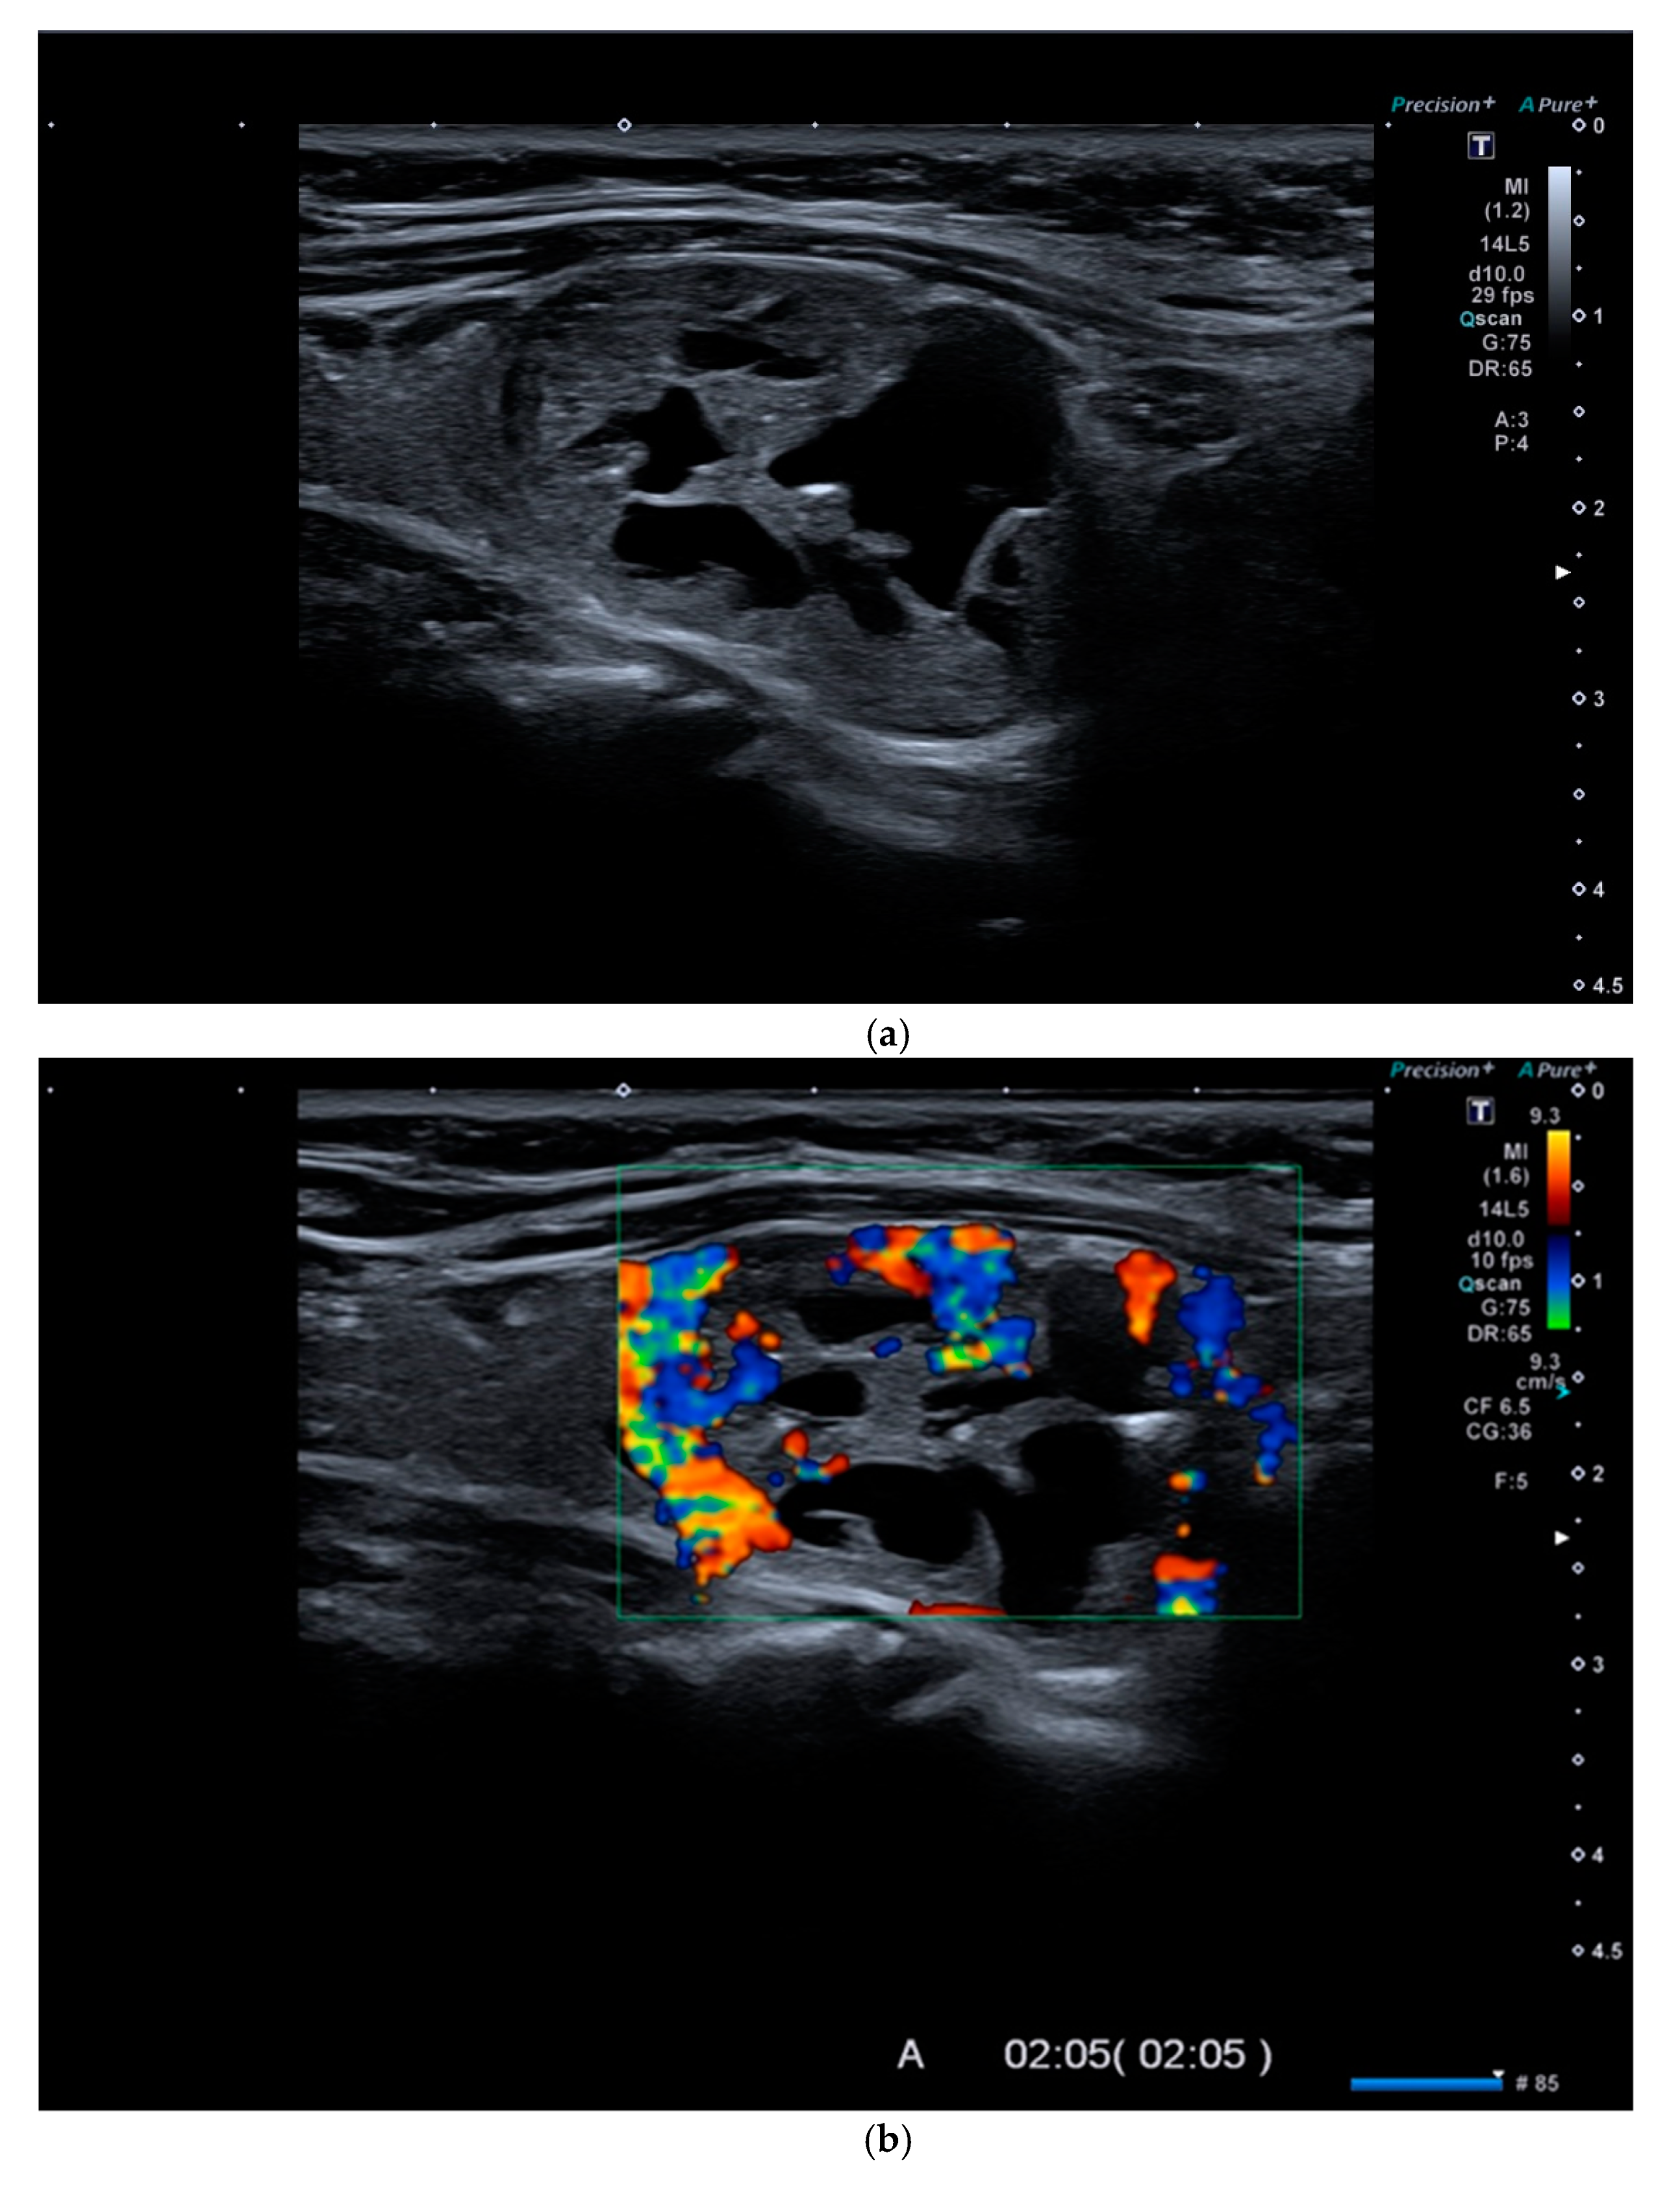

4. Color-Doppler

6. Multiparametric Ultrasound

Multiparametric Ultrasound (MPUS) Role for Indeterminate Thyroid Nodule Evaluation